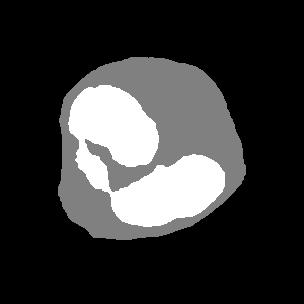

4.2.2 Drosophila Cell Image

Drosophila cell image [6] consists of 20 images including 4 classes of cell membrane, cytoplasm, mitochondria, and synapses with an image size of 1024×1024102410241024\times 1024 pixels. In experiment, we divided the images into 12 training images, 3 validation images, and 5 test images, and divided the original image size into 16 regions of 256×256256256256\times 256 pixels without overlap. The final number of images was 192 for training, 48 for validation, and 60 for evaluation. The batch size is set to 4 for training. In the segmentation images, red indicates cell membrane, black indicates cell membrane, green indicates mitochondria, and blue indicates synapses.

Figure 6: Segmentation results on Drosophila dataset

4.3.2 Results on Drosophila Cell Images

As shown in Table 3, the proposed method improved the accuracy compared to the conventional methods in many classes. In particular, our proposed AML-Net and Top-Down PDA-Module improved the accuracy of synapses, which is the most difficult class. Top-Down PDA-Module is a top-down attention mechanism using ground-truth, and it is considered that the accuracy is improved due to its ability to create attention maps that explicitly strengthen particularly difficult synapses. In addition, the accuracy of ATA-Module was improved in many classes compared to conventional methods. From the feature maps obtained from the discriminator, it can be concluded that the ATA-Module contributes to the accuracy improvement because the similarity between pixels is appropriately enhanced by the ATA-Module. Therefore, AML-Net with the appropriate combination of Top-Down PDA-Module and ATA-Module can improve the accuracy of IoU for many classes. Deeplabv3+ with ResNet-50 as its backbone does not train well on Drosophila cell images, indicating that even successful models for scene segmentation are not effective for cell image segmentation. In addition, AML-Net has better IoU accuracy than FastFCN using ResNet-50.

The top image group in Figure 6 shows that Top-Down PDA-Module and AML-Net can accurately detect synapses that are easily over-detected by conventional methods. However, our method also caused excessive false positives for cell membrane and mitochondria on the right side. The false positives were probably caused by the fact that the input image shows something very similar to cell membrane and mitochondria. In the lower group of images, U-Net and Top-Down PDA-Module fail to detect mitochondria, and misidentify them as mitochondria in some cell membranes, while ATA-Module and AML-Net correctly identify mitochondria, reducing the number of undetected or false positives. Thus, we can see that AML-Net is able to recognize mitochondria by utilizing the advantages of both ATA-Module and Top-Down PDA-Module.